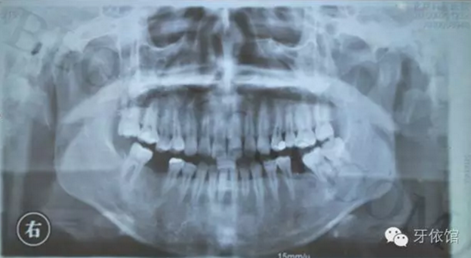

患者:女,28歲,此x光片為4年前拍的,左下6已于四年前行種植修復(fù),今天主要介紹右下6種植修復(fù)過程。計劃微創(chuàng)種植。